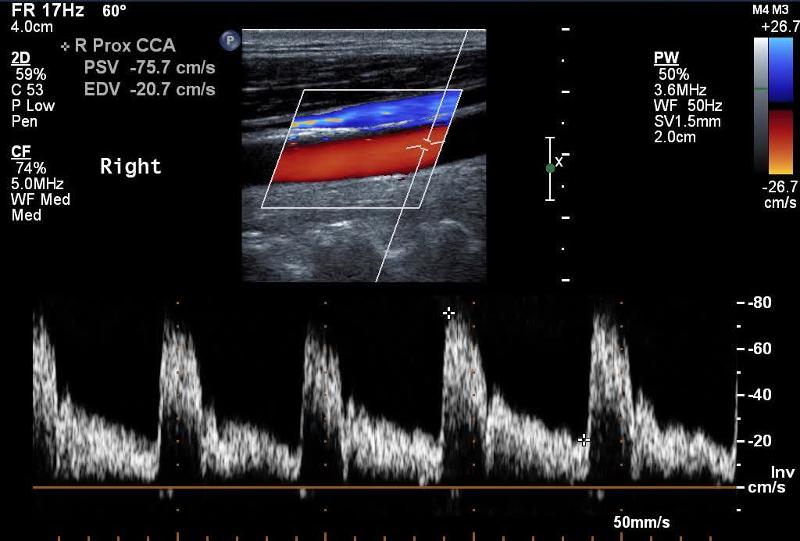

Explain the waveform of the CCA

Mimics both ICA and ECA waveforms

Explain the waveform of the ICA

low resistant - constant forward flow

Forward flow throughout the cardiac cycle

Where is peak systole?

The highest point on the wave form

Where is end diastole?

The point just prior to the systolic upstroke

Where is the waveform?

CCA